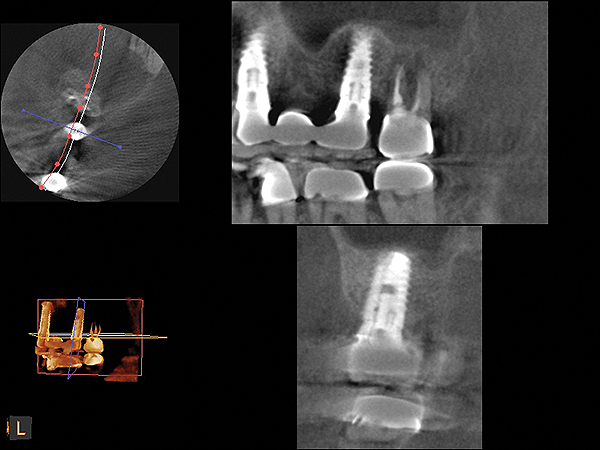

A 74-year-old male patient presented with about 4 mm to 5 mm of native bone in the No. 4 position (Figure 17). A composite graft, as described in Case 1, was used, as was the same implant type, but the implant was 11.5 mm in length with a taper of 5 mm to 4.2 mm. The approximately 16-month post-healed floor of the sinus was raised about 7 mm to 8 mm (Figure 18). The CBCT scan taken at 16 months postoperatively showed no change in appearance from the area of the old floor of the sinus to the new bone formed (Figure 19). Although it was endodontically involved, tooth No. 15 was not extracted, against professional advice. As can be seen in Figure 18, the No. 14 implant is acting as a bridge abutment.

Fig 19. CBCT scan (Kodak 9000D) of implant No. 14 showing homogeneous appearance of the bone.

Figure 19